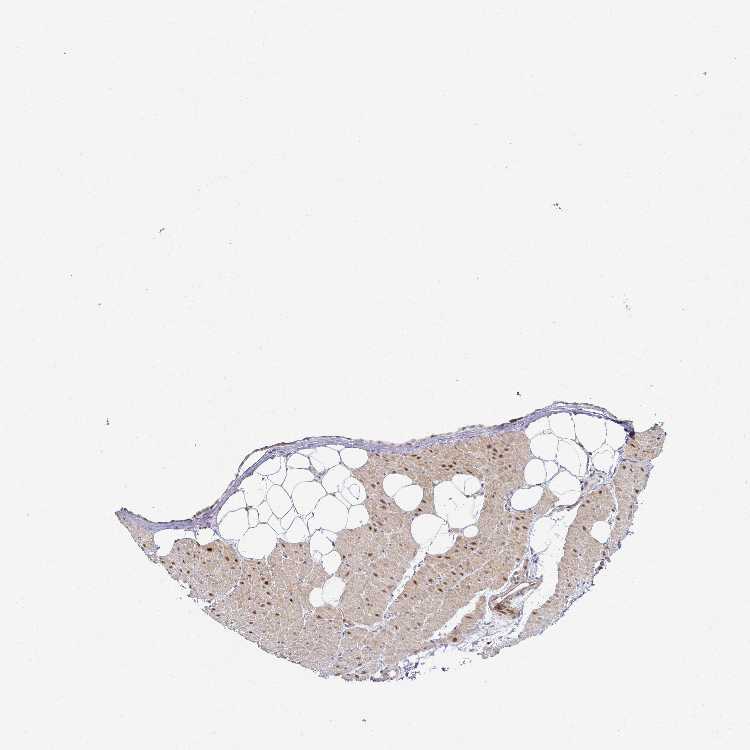

HEART MUSCLE - Antibody stainingi

Antibody staining in the annotated cell types in the current human tissue is reported as not detected, low, medium, or high, based on conventional immunohistochemistry profiling in selected tissues. This score is based on the combination of the staining intensity and fraction of stained cells.

Each image is clickable and will lead to virtual microscopy that enables deeper exploration of all samples and also displays staining intensity scores, fraction scores and subcellular localization as well as patient and tissue information for each sample.

Antibody HPA049824Antibody HPA056069Antibody CAB019379

Cardiomyocytes HighHighMedium